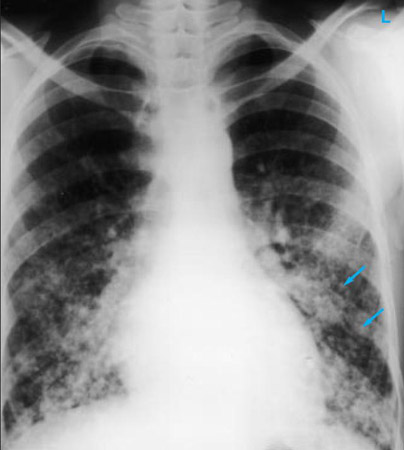

Chest x-ray

A chest x-ray should be obtained early in the evaluation of chronic cough.[38] Although it is not diagnostic of the most common causes, findings may quickly divert the evaluation to causes of greater gravity, such as structural lung diseases. These include lung cancer, pulmonary fibrosis, tuberculosis, bronchiectasis, pneumonia, aspiration, and sarcoidosis.[Figure caption and citation for the preceding image starts]: Chest x-ray showing hyperinflation in a patient with COPD. The hyperinflation is caused by the emphysema component of COPD, rather than the chronic bronchitis that underlies symptoms of coughFrom the personal collection of Dr M. A. Sharifabadand, SUNY at Stony Brook School of Medicine, Department of Pulmonary and Critical Care Medicine, Mineola, New York and Dr J. P. Parsons, The Ohio State University Medical Center, Columbus; used with permission [Citation ends].com.bmj.content.model.assessment.Caption@65a65855[Figure caption and citation for the preceding image starts]: Chest x-ray showing multiple miliary lung metastases (arrows). The primary tumour was a thyroid carcinomaE. Dick, Student BMJ. 2001;9:10-12 [Citation ends].com.bmj.content.model.assessment.Caption@25657fee[Figure caption and citation for the preceding image starts]: Chest x-ray showing left hilar carcinoma (arrow)From: E. Dick, Student BMJ. 2000;8:358-360 [Citation ends].com.bmj.content.model.assessment.Caption@567b9fef[Figure caption and citation for the preceding image starts]: Chest x-ray showing a cavitating right hilar carcinoma (arrow)E. Dick, Student BMJ. 2001;9:10-12 [Citation ends].com.bmj.content.model.assessment.Caption@3d6fa55[Figure caption and citation for the preceding image starts]: Chest x-ray in a patient with bronchogenic carcinoma showing a left-sided pleural effusionFrom: R. Thakkar, Student BMJ. 2001;9:458 [Citation ends].com.bmj.content.model.assessment.Caption@5b46acec[Figure caption and citation for the preceding image starts]: Chest x-ray showing interstitial fibrosis in a patient with amiodarone pulmonary toxicityFrom the personal collection of Dr A. Pataka and Professor P. Argyropoulou, Aristotle University, Thessaloniki, Greece; used with permission [Citation ends].com.bmj.content.model.assessment.Caption@2c3c94b0[Figure caption and citation for the preceding image starts]: Chest x-ray showing pulmonary tuberculosis with cavitationFrom the personal collection of Dr M. Narita, Department of Pulmonary and Critical Care Medicine, University of Washington [Citation ends].com.bmj.content.model.assessment.Caption@3dd7f84b[Figure caption and citation for the preceding image starts]: Chest x-ray showing multiple discrete nodules throughout both lungs (one of which is circled) in a patient with miliary tuberculosisE. Dick, Student BMJ. 2001;9:10-12 [Citation ends].com.bmj.content.model.assessment.Caption@23fa6365[Figure caption and citation for the preceding image starts]: Chest x-ray with lack of normal tapering producing a tram line in a patient with bronchiectasisFrom the personal collection of Dr S.M. Bhorade, University of Chicago Medical Center; used with permission [Citation ends].com.bmj.content.model.assessment.Caption@36b415f2[Figure caption and citation for the preceding image starts]: Chest x-ray with dilated and thickened airways in a patient with bronchiectasisFrom the personal collection of Dr S.M. Bhorade, University of Chicago Medical Center; used with permission [Citation ends].com.bmj.content.model.assessment.Caption@78e208fa[Figure caption and citation for the preceding image starts]: Chest x-ray showing increased opacification of the right perihilar region and superior segment of the right lower and upper lobes consistent with worsening aspiration pneumoniaFrom the personal collection of Dr R. Kanner, University of Utah School of Medicine [Citation ends].com.bmj.content.model.assessment.Caption@71be2c1f[Figure caption and citation for the preceding image starts]: Portable chest x-ray with bibasilar opacities, worse on the right than the left, in a patient with hospital-acquired pneumoniaFrom the personal collection of Dr F. W. Arnold, Division of Infectious Diseases, Department of Medicine, University of Louisville School of Medicine [Citation ends].com.bmj.content.model.assessment.Caption@2c704497[Figure caption and citation for the preceding image starts]: Chest x-ray showing early ill-defined opacities of the right upper lobe above the minor fissure consistent with early changes of aspiration pneumoniaFrom the personal collection of Dr R. Kanner, University of Utah School of Medicine [Citation ends].com.bmj.content.model.assessment.Caption@23fa54d0[Figure caption and citation for the preceding image starts]: A. Portable upright chest x-ray before aspiration; B. Chest x-ray 1 hour after aspiration, showing bilateral diffuse alveolar infiltrates, worse at the bases on the right sideFrom the personal collection of Dr S. Murgu and Dr H. Colt, University of California at Irvine Medical Center [Citation ends].com.bmj.content.model.assessment.Caption@7860be3a[Figure caption and citation for the preceding image starts]: Chest x-ray showing bilateral hilar adenopathy in a patient with sarcoidosisFrom the personal collection of Dr M.P. Muthiah, Division of Pulmonary and Critical Care and Sleep Medicine, University of Tennessee [Citation ends].com.bmj.content.model.assessment.Caption@31e94b4e